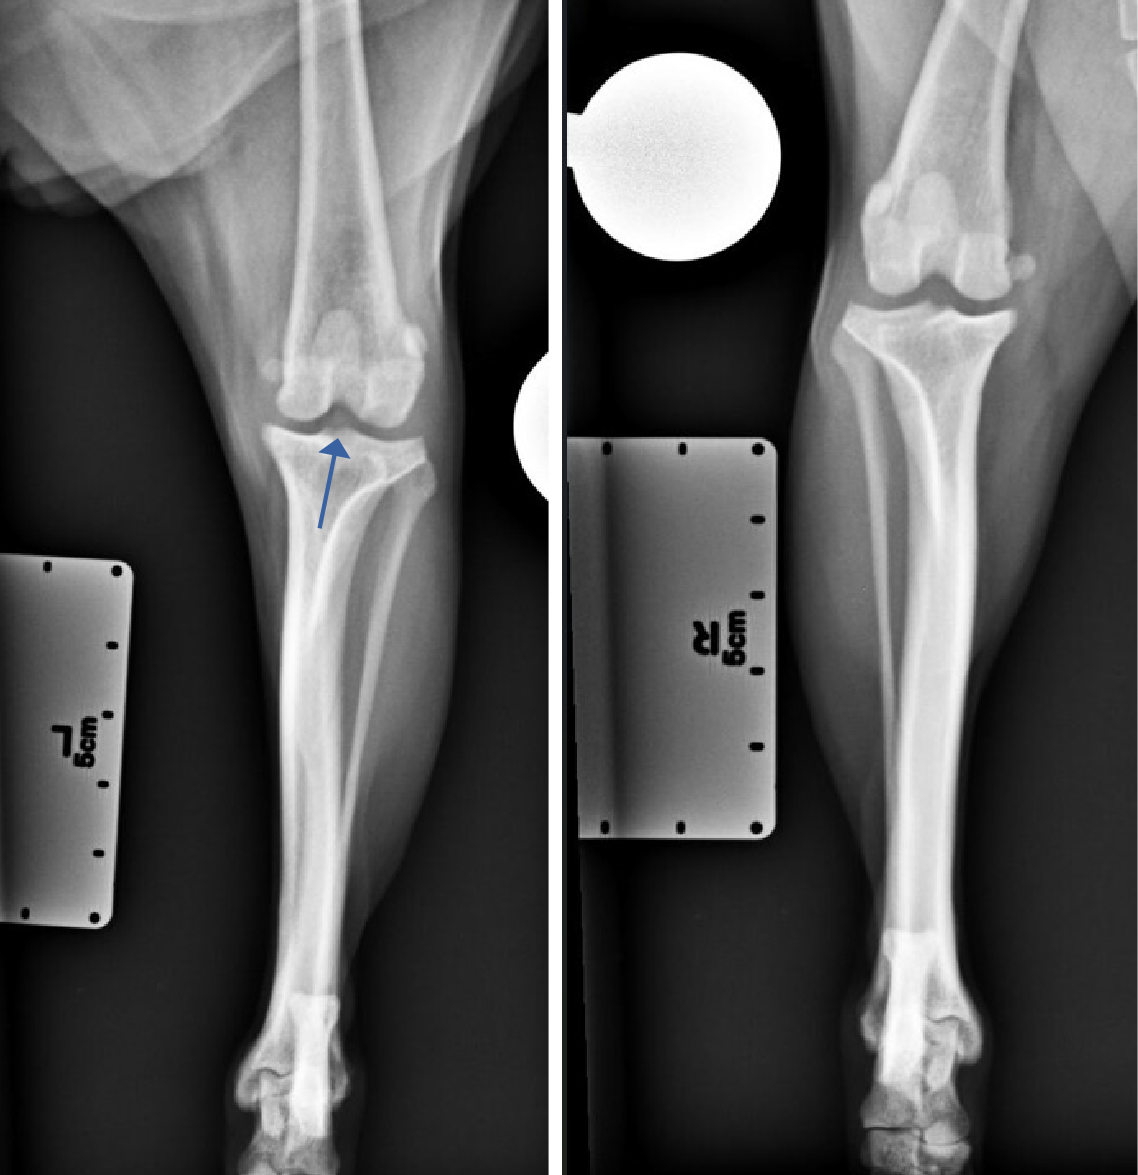

Figur 3 og 4. Kraniokaudal projeksjon av venstre og høyre kneledd og haseledd. I venstre kneledd var det tegn på effusjon (pil).

Laterolateral projeksjon og kraniokaudal projeksjon av hundens høyre og venstre kneledd, tibia, fibula og tarsalledd var tilgjengelig for vurdering. Kvaliteten på bildene var akseptabel. Det ble funnet tydelig effusjon i venstre kneledd med et brattere tibiaplatå enn ved høyre kne. Venstre kne hadde tegn på osteofyttdannelse på apex patella og femoral ridge som tydet på tidlig osteoartoseforandringer. Tibiaplatå vinkelen (TPA) ble målt til 26,2 grader. Denne vinkelen måles mellom en perpendikulær linje til lengdeaksen av tibia og en linje parallell til tibiaplatået. En større tibiaplatåvinkel resulterer i større kranial kraft av tibia under vektbæring. Det kunne ikke påvises annen patologi utifra disse bildene.